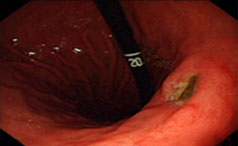

常见症状:出现餐后嗳气、恶心、腹胀

反复发作性剧烈腹痛、上消化道少量出血

不容小觑的胃溃疡,一文了解,牡丹江附大胃肠病医院【官网预约挂号:13206882659(微同号)】胃溃疡虽常见,但了解其症状、成因、危害及防......【详情】

常见症状:体重减轻、疼痛、出血

上腹部压痛